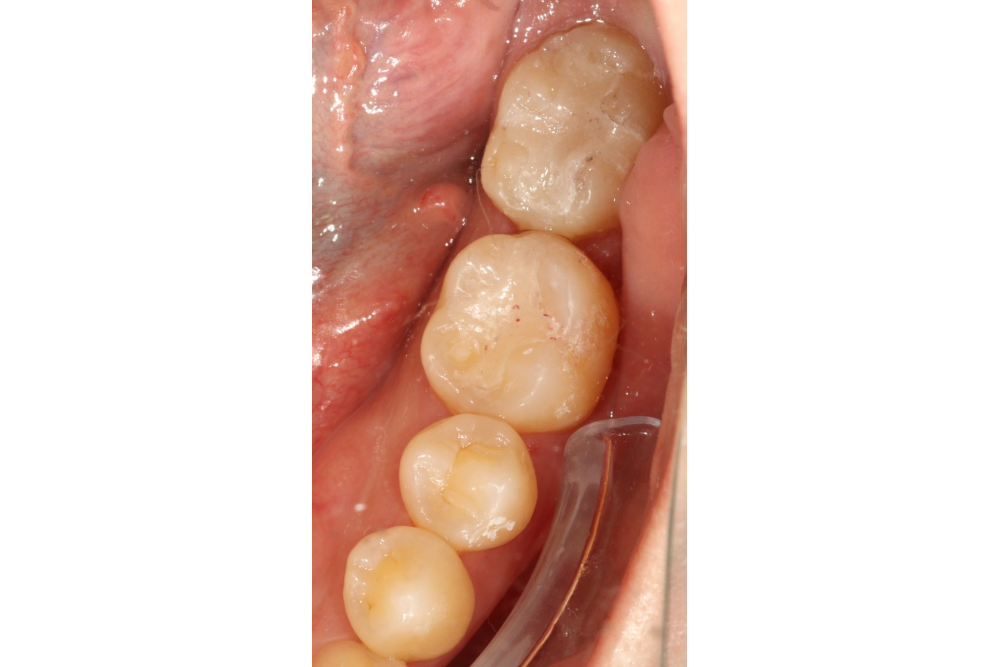

부분교정을 통해 누워있던 사랑니를 세웠으나, 씹는 면에 충치가 있습니다.

교정종료 후 보철치료(인레이)를 통해 씹는 기능을 회복시켰습니다.

누워있던 이가 세워져서 음식물이 더 잘 씹히게 되었습니다.

또한 음식물이 끼지 않게 되어 구강위생관리도 원활하게 되었습니다.